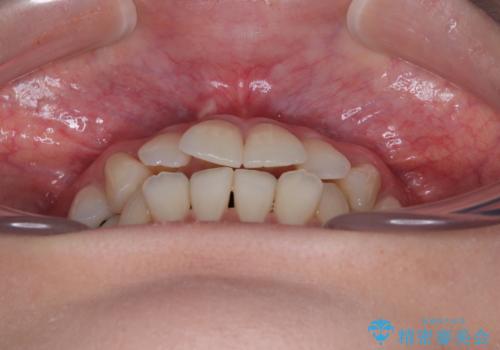

【モニター】前歯のデコボコをインビザラインで綺麗に

- 上下前歯のデコボコとクロスバイトを気にして来院された患者様です。

治療済みの処置歯が多いため、インビザラインを用いて矯正治療を行うこととしました。

下顎臼歯部にブリッジが装着されており、移動不可のため、IPR(歯と歯の間を削る)と歯列全体を拡大させることで、歯並びを整えていくこととしました。

インビザライン特有の奥歯の噛みにくさが治療後半に発現しましたが、無事に終了させることができました。